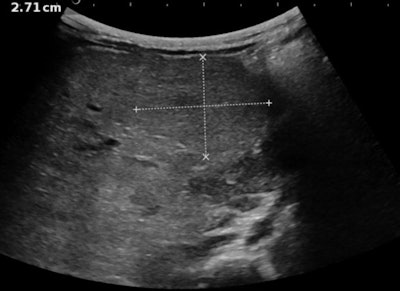

In adults, a tumor may be discovered in follow-up of known cirrhosis or liver disease. In children, however, the tumor itself is often the first pathology that is discovered, usually with ultrasound, but this may be a lesion related to other diagnoses. Finding the underlying causes favoring the development of pediatric liver tumors remains one of Franchi-Abella's personal crusades, and the role of ultrasound should not be underestimated, she noted.

For children, multiparametric liver ultrasound to show tumoral and nontumoral liver is the first line of deeper investigation, after the initial diagnosis of a liver mass. Different techniques should be used including grayscale, Doppler, elastography for fibrosis, Micro-Doppler to discern the vascularization of the tumor, and contrast-enhanced ultrasound to assess tumor behavior, and differentiate between malignant and benign lesions.